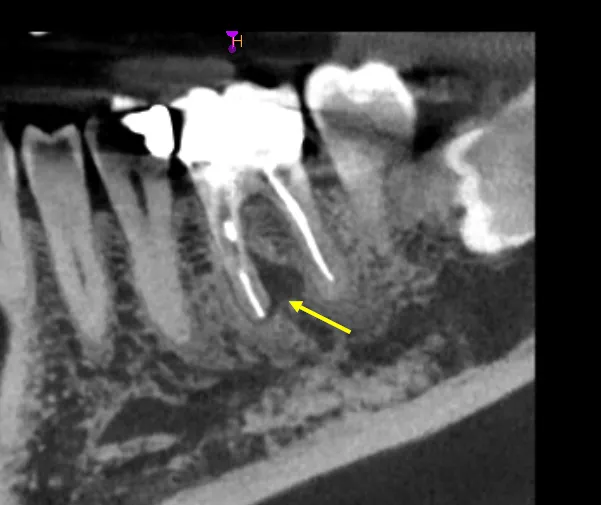

The referring dentist had searched for the distal canal, drilled too far lingually, and created a 2mm perforation directly into the furcation. The patient presented with active bleeding from the perforation site and understandable anxiety about losing the tooth.

At 3-year follow-up, this tooth shows excellent healing:

• Radiographic evidence of bone maintenance at perforation site